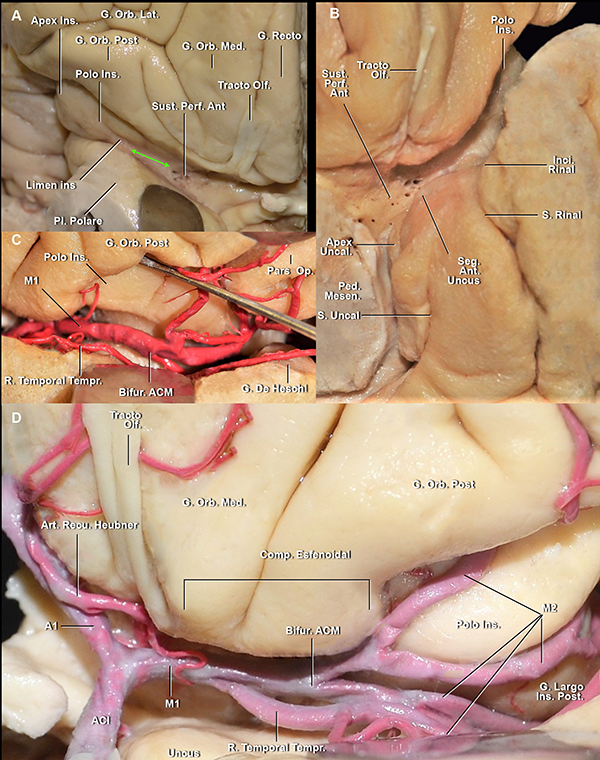

Figura 1: A. Vista anterior de la superficie basal de una FS derecha. La parte más profunda de la FS en la superficie basal está conformada por el compartimiento operculoinsular anterior. El receso del limen (flecha verde) es el espacio entre el punto más lateral en el que una arteria perforante entra a la SPA y el borde medial del limen insular. B. Vista anteroinferior de un hemisferio cerebral izquierdo. Las estructuras neurales que marcan el límite medial de la parte basal de la cisterna silviana son el tracto olfatorio y la incisura rinal. El uncus se localiza medialmente a la incisura rinal, en relación con la cisterna carotídea. C. Mismo espécimen que en B, vista anterolateral. El disector se ubica en la hendidura insular anterior. En este espécimen la bifurcación de ACM se localiza en el limen insular. Se observa una arteria temporal temprana naciendo de M1. D. Vista anteroinferior de la superficie basal de una FS izquierda. El compartimiento esfenoidal se extiende desde la cisterna carotídea hasta el limen insular. La bifurcación carotídea y la mitad proximal de M1 y A1, se localizan en la cisterna carotídea. El segmento anterior del uncus se enfrenta al segmento proximal de M1. G: giro; Orb: orbitario; Ins: insular; Lat: lateral; Post: posterior; Ant: anterior; Med: medial; Pl: plano; Perf: perforante; Olf: olfatorio; Sust: sustancia; S: surco; Inci: incisura; Seg: segmento; Ped: pedúnculo; Mesen: mesencefálico; R: ramo; Tempr: temprano; Bifur: bifurcación; Art: arteria; Recu: recurrente; comp: compartimiento.

La parte profunda de la FS tiene una organización más compleja. La parte cisternal en la superficie basal del cerebro se extiende desde la estría olfatoria lateral hasta el limen insular (Figura 1A). Está compuesta por 1) el compartimiento opercular anterior, en un nivel intermedio de profundidad, y 2) la hendidura insular anterior y el compartimiento esfenoidal, en el nivel más profundo (Figura 1).

El compartimiento opercular anterior se define como el espacio entre los giros orbitarios posterior y lateral y el plano polar del lóbulo temporal (Figura 5A y 6B). Por otro lado, la hendidura insular anterior se localiza entre la ínsula y los giros orbitarios lateral y posterior (Figura 1C,6B,7A).

El compartimiento esfenoidal presenta una disposición de inferomedial a superolateral. El extremo medial del compartimiento está delimitado por la membrana aracnoidea silviana proximal, que lo separa de la cisterna carotídea y es perforada por el segmento proximal de M1 de la ACM (Figura 8B). La membrana aracnoidea silviana proximal está adherida a la estría olfatoria lateral y a la incisura rinal, o también llamada incisura temporal (Figura 1B y 8B). El segmento anterior del uncus se ubica medial a la membrana silviana proximal. El techo del compartimiento esfenoidal está compuesto por la sustancia perforada anterior (SPA) y los giros fronto-orbitarios. El núcleo caudado y lentiforme, así como también el brazo anterior de la cápsula interna, se localizan por encima del techo de este compartimiento. La pared posterior del compartimiento esfenoidal es el área donde la SPA se fusiona con el lóbulo temporal. El limen insular es su límite lateral (Figura 1A y B). El receso del limen, que es el área comprendida entre la arteria lentículo estriada más lateral y el limen insular, fue hallado en todos los hemisferios estudiados en este trabajo y midió un promedio de 12 mm de largo (Figura 1A). Este receso es un espacio desprovisto de arterias perforantes. El piso del compartimiento esfenoidal es el plano polar. Este compartimiento contiene principalmente: la mitad distal del segmento M1, las arterias perforantes de la SPA, las ramas corticales tempranas de la ACM, los troncos arteriales post bifurcación que pudieran nacer de este segmento si la bifurcación de la ACM fuera proximal al limen insular, la parte distal de la arteria recurrente de Heubner y la vena cerebral media profunda (Figura 1B y D).

El segmento M1 se origina en la cisterna carotídea y se relaciona superiormente con la SPA e inferiormente con el segmento anterior del uncus (Figura 1D). Este segmento perfora la membrana silviana proximal y entrando al compartimiento esfenoidal de la cisterna silviana. En este segmento, se identificaron el origen tanto de las arterias lenticuloestriadas como de las ramas corticales tempranas (Figura 1C y D). En nuestra serie, 9 de los 10 hemisferios presentaron por lo menos una rama cortical temprana.